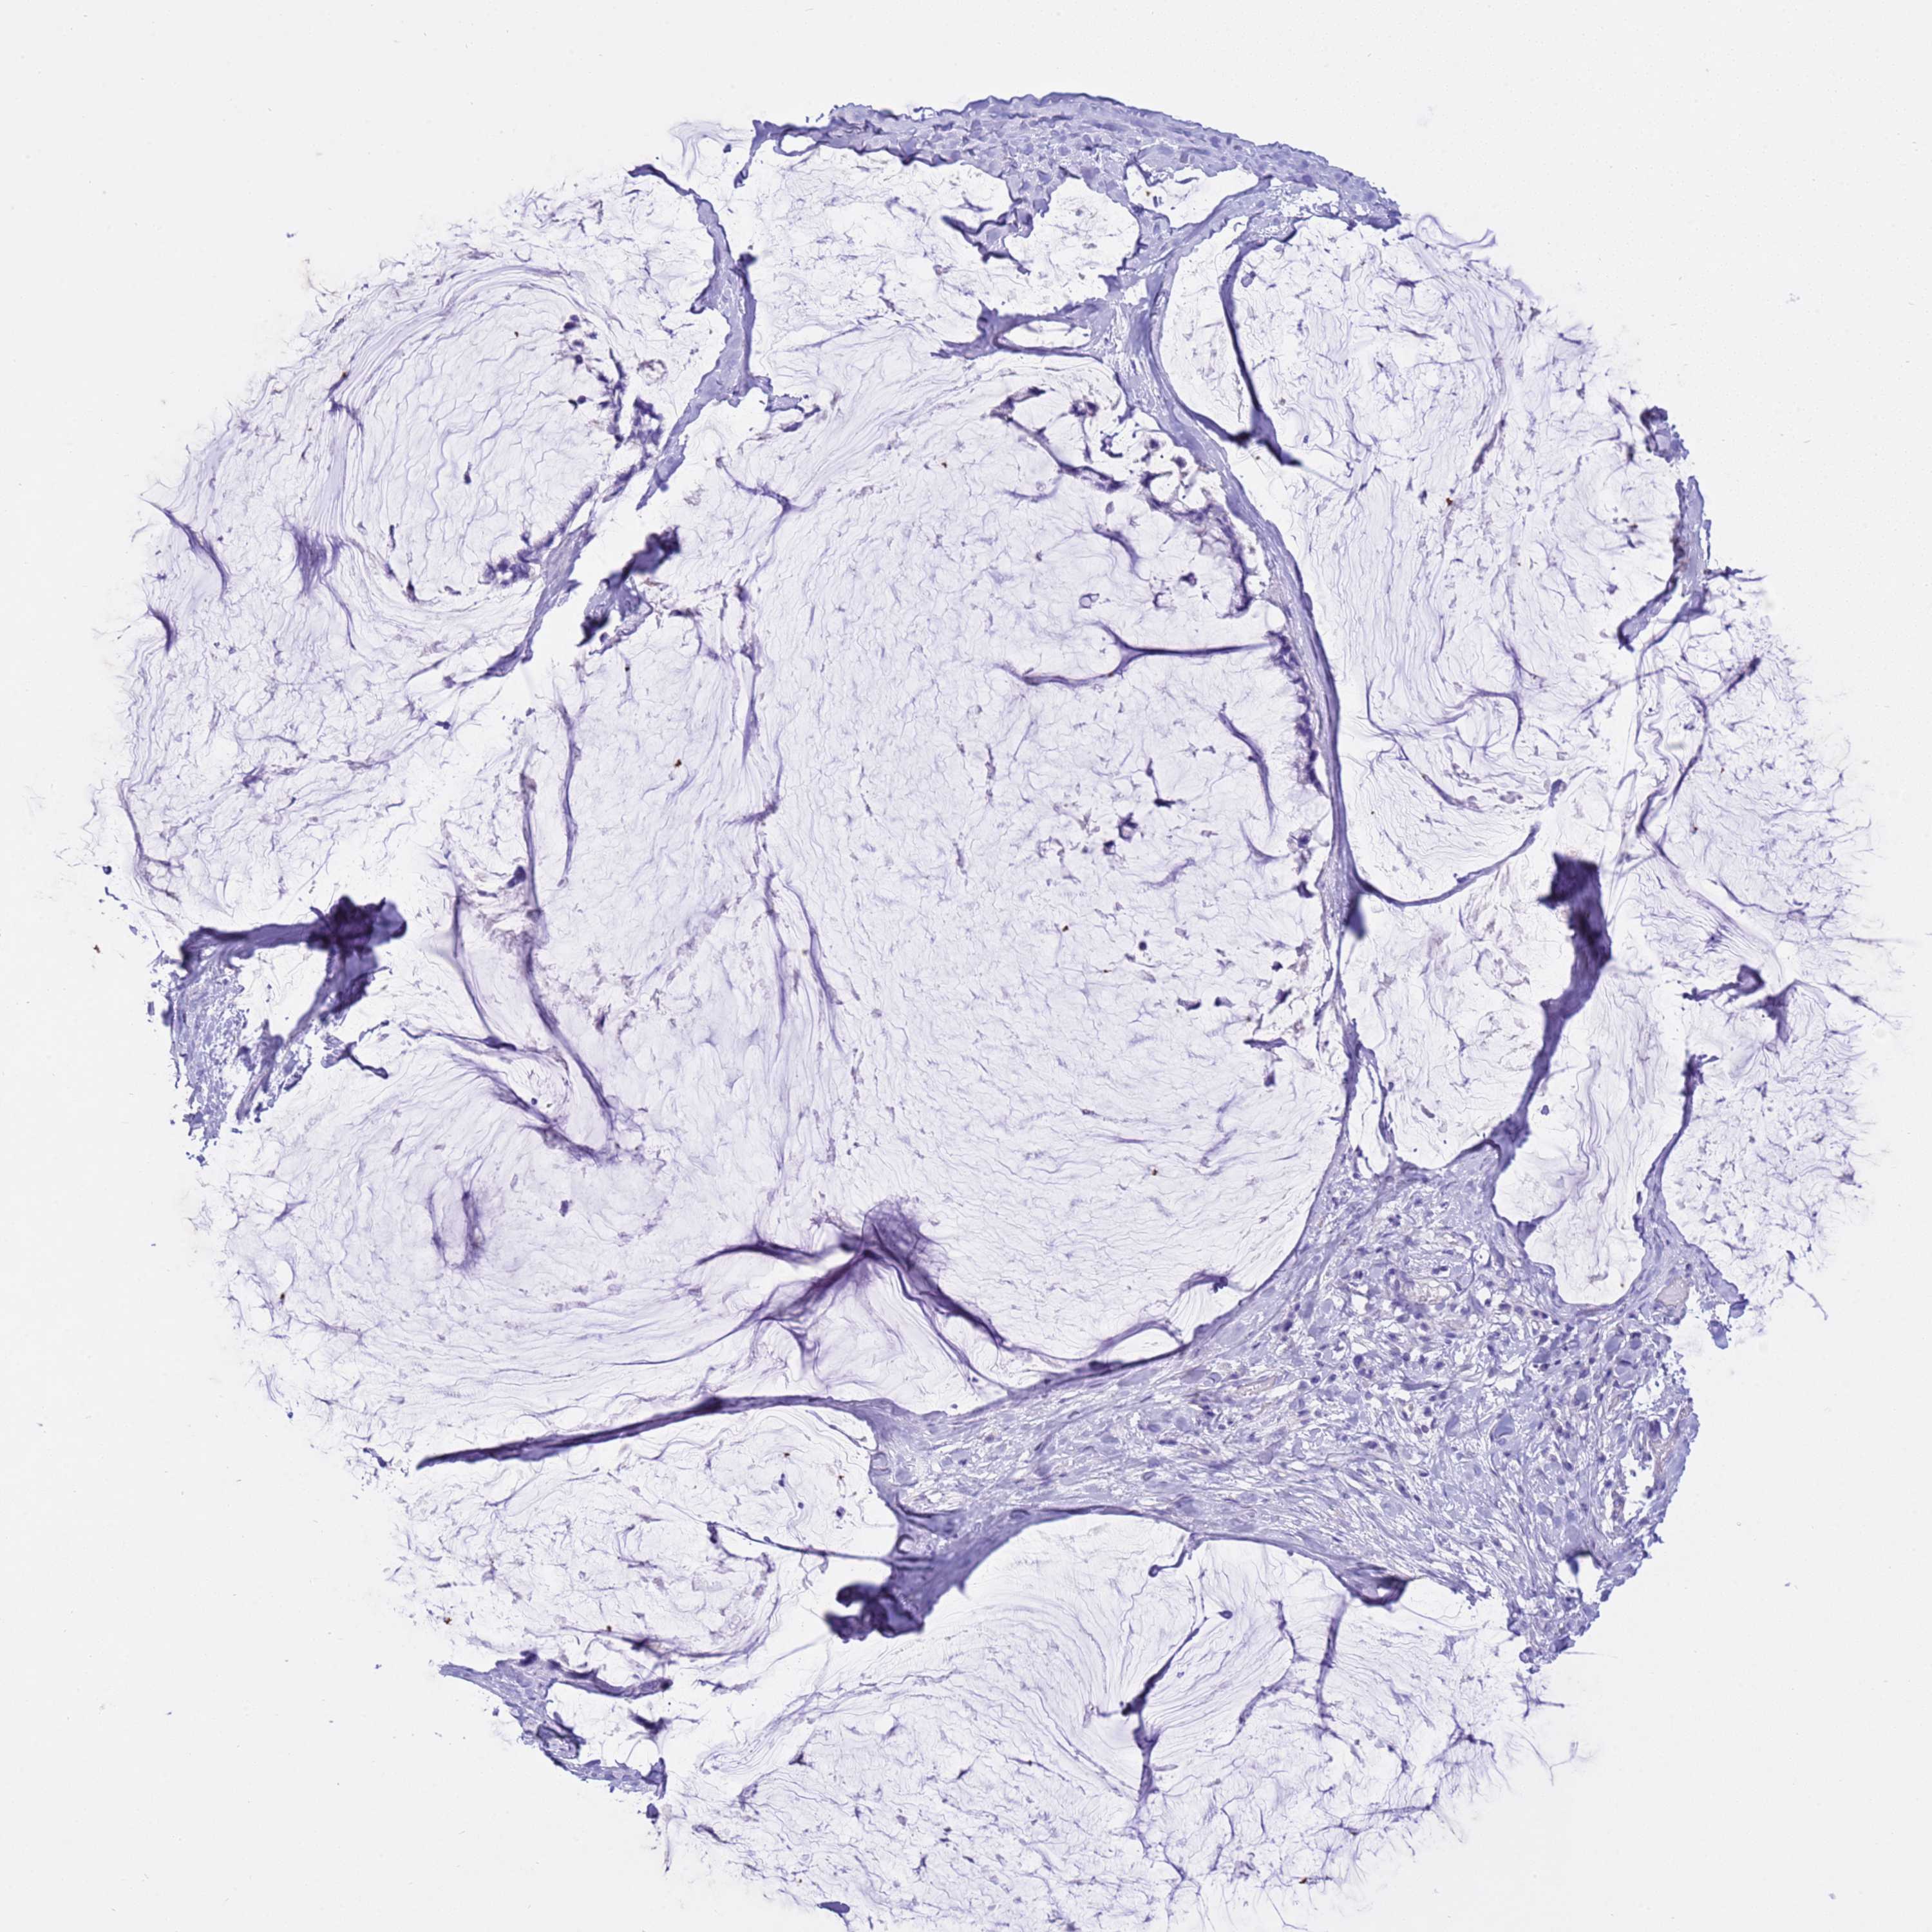

OVARIAN CANCER - Protein expressioni

A mouse-over function shows sample information and annotation data. Click on an image to view it in a full screen mode. Samples can be filtered based on level of antibody staining by selecting one or several of the following categories: high, medium, low and not detected. The assay and annotation is described here.

Note that samples used for immunohistochemistry by the Human Protein Atlas do not correspond to samples in the TCGA dataset.

Antibody stainingi

Antibody staining in the annotated cell types in the current human tissue is reported as not detected, low, medium, or high, based on conventional immunohistochemistry profiling in selected tissues. This score is based on the combination of the staining intensity and fraction of stained cells.

Each image is clickable and will lead to virtual microscopy that enables deeper exploration of all samples and also displays staining intensity scores, fraction scores and subcellular localization as well as patient and tissue information for each sample.

Antibody HPA038069

Antibody HPA046340

Antibody CAB026158

Cystadenocarcinoma, serous, NOS

Carcinoma, endometroid

Cystadenocarcinoma, mucinous, NOS

Carcinoma, NOS